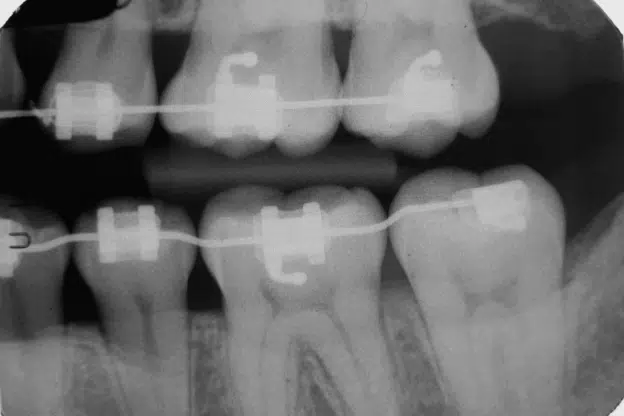

Orthodontic decisions are guided by clinical evaluation rather than trends or personal preference. Before recommending any appliance, orthodontists assess how teeth align within the jaw, how the bite functions during everyday activities, and how much mechanical control is required to guide movement safely. While many patients know there are multiple alignment options available, the final decision is rooted in diagnostics, biology, and long-term oral health rather than appearance alone. In certain cases, metal braces are selected when orthodontists determine that a fixed system is necessary to achieve predictable and controlled results. This type of braces recommendation is based on how teeth reposition within bone and how the upper and lower jaws interact under functional pressure. This article explains the clinical criteria orthodontists use when deciding whether a fixed orthodontic appliance is appropriate and how those decisions support effective, stable outcomes over time. Clinical Evaluation as the Starting Point Every orthodontic...